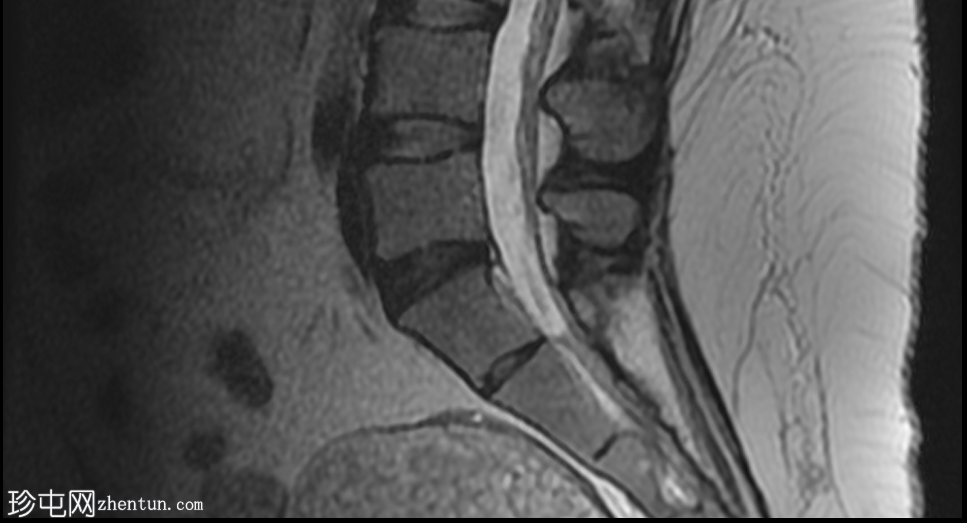

2.jpeg

矢状位

平扫

可见一主要为囊性肿块,大小为10.1 x 7.3 x 8厘米,囊内含有脂肪球。囊壁可见钙化,并对直肠乙状结肠造成压迫。